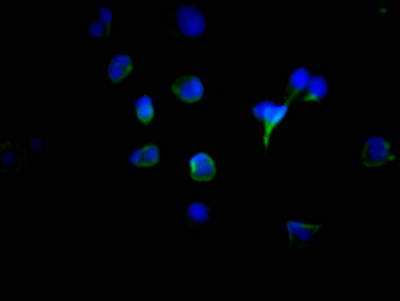

Immunofluorescence staining of MCF7 Cells with CSB-RA567167A0HU at 1:50, counter-stained with DAPI. The cells were fixed in 4% formaldehyde, permeated by 0.2% TritonX-100, and blocked in 10% normal Goat Serum. The cells were then incubated with the antibody overnight at 4℃. Nuclear DNA was labeled in blue with DAPI. The secondary antibody was FITC-conjugated AffiniPure Goat Anti-Rabbit IgG (H+L).